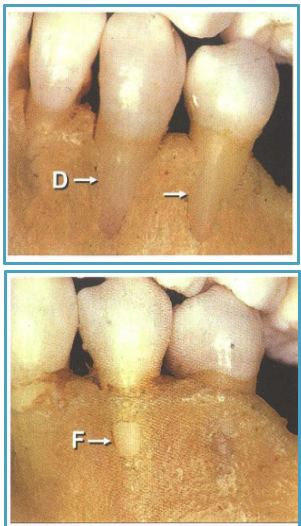

what are 2 alveolar bone defects

fenestration: exposed root due to absence of lingual/buccal alveolar bone lamina

dehiscence: roots extending through marginal bone

alveolar bone defects are more common on facial or lingual

facial

common areas of fenestrations vs. dehiscence

fenestration: maxilla

dehiscence: mandible